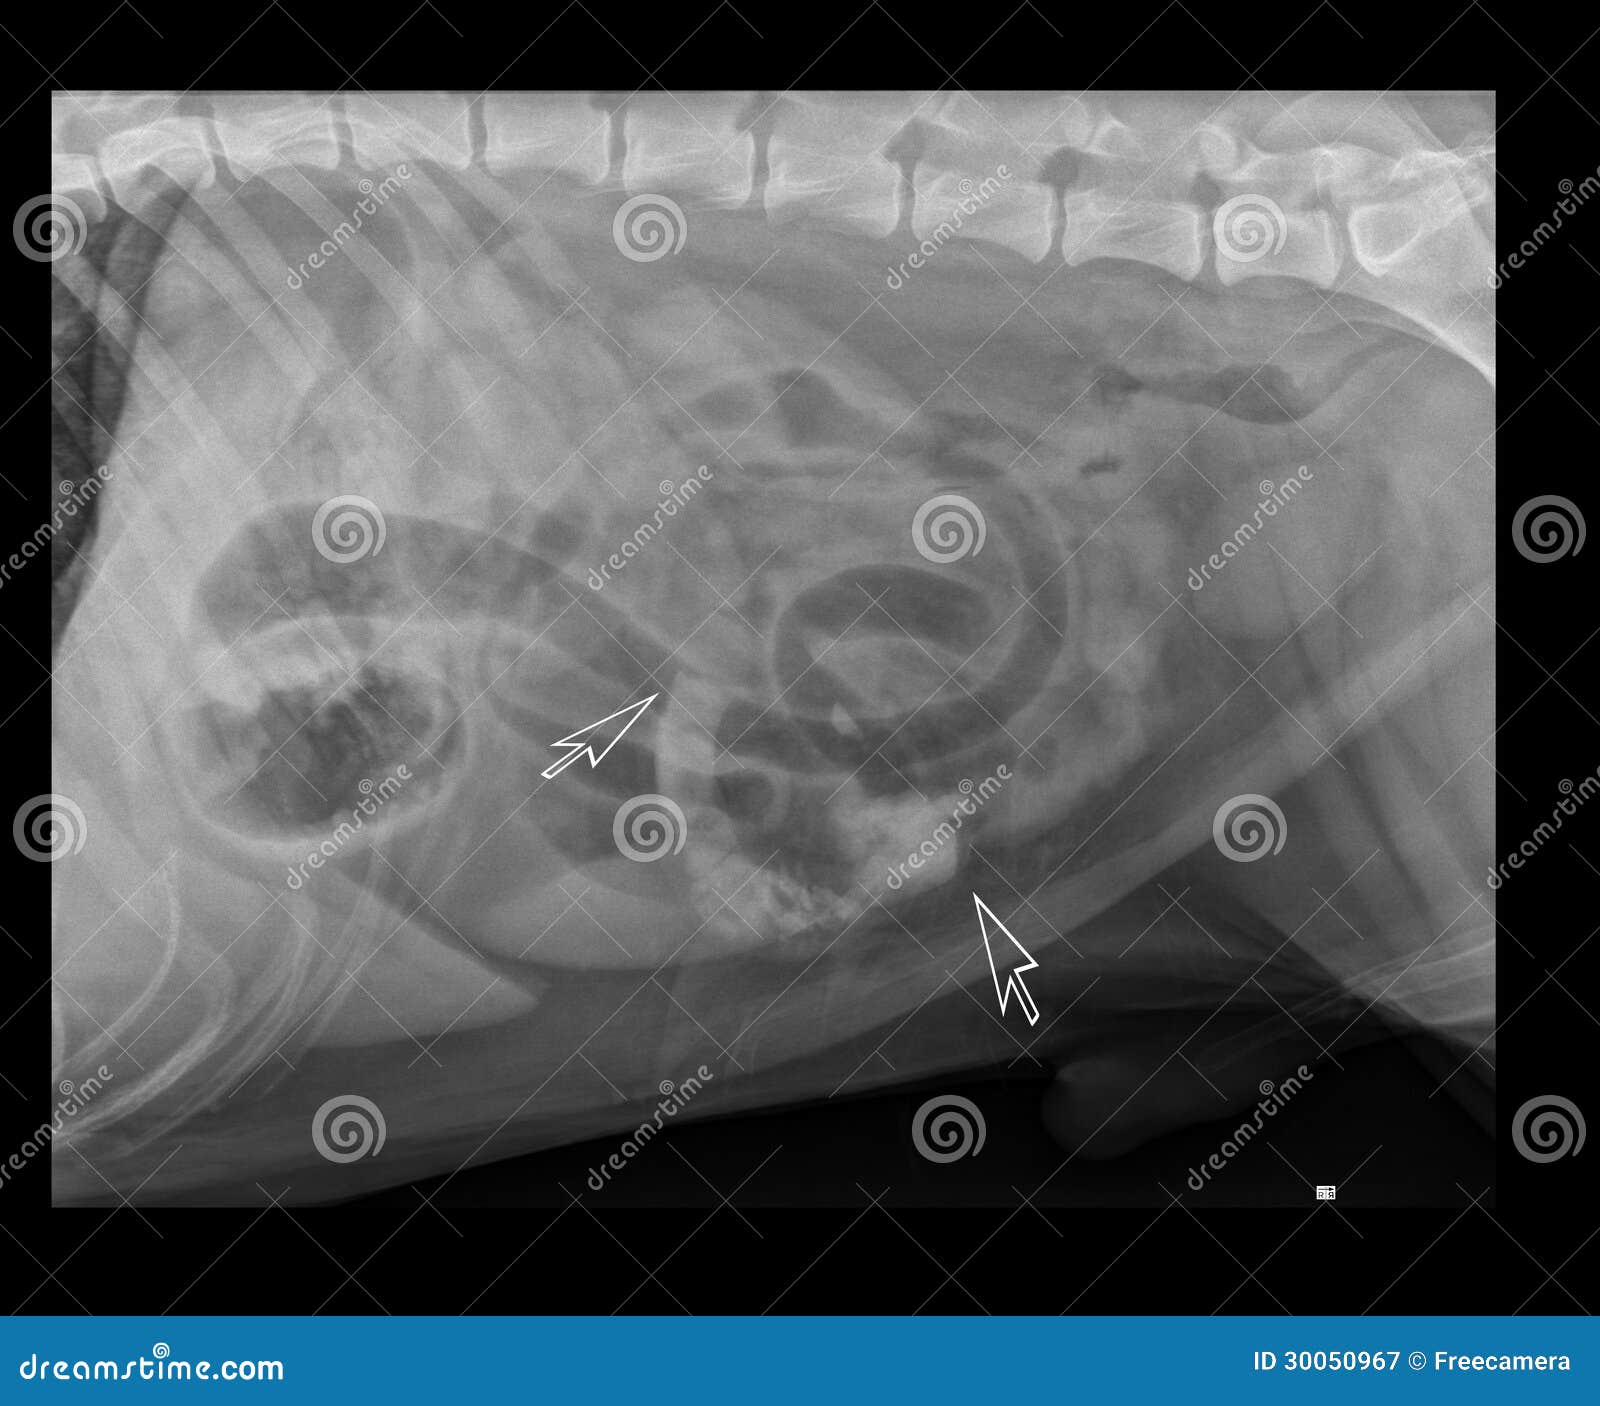

Существуют инородные тела рентгеноконтрастные – они визуализируются на рентгене, и не рентгеноконтрастные – они не визуализируются на рентгене (например, дерево). Дополнительное введение рентгеноконтрастных веществ (сульфат бария, йодсодержащие препараты), при проведении рентгена пищевода и желудка, позволяют в некоторых случаях определить не рентгеноконтрастные инородные тела (фото 1).

- Рентгенография – позволяет рассмотреть петли тонкого кишечника, располагающиеся в центральной зоне брюшной полости в двух проекциях – вентродорсальная и боковая. Аномальное расширение исследуемого материала сигнализирует о растяжении от постороннего предмета или от иных причин. На снимке можно обнаружить металлические вещи, кости, камни, стекло. Впрочем, не всегда инородные тела видны с помощью рентгенографии. Так, сложно обнаружить на снимке нитки, резиновые изделия, полиэтилен или тряпку. В этом случае применяют контрастную рентгенографию или другие способы исследования.